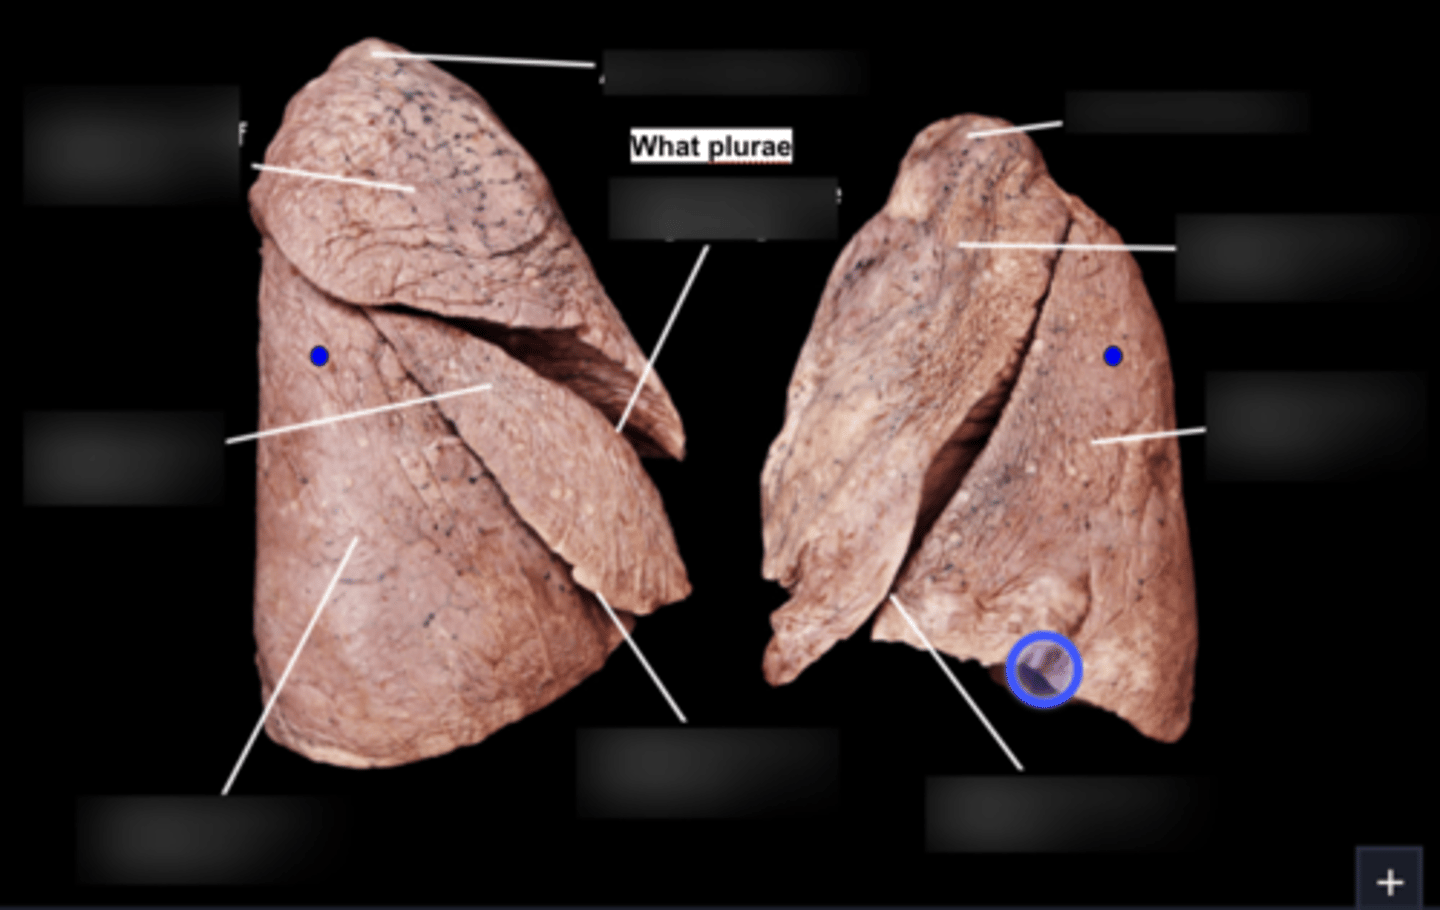

Superior lobe of left lung

Inferior lobe of left lung

Lingula

Apex

Base/Diaphragmatic Surface

Costal Surface

Mediastinal Surface

Anterior Margin

Posterior Margin

Visceral Plurae